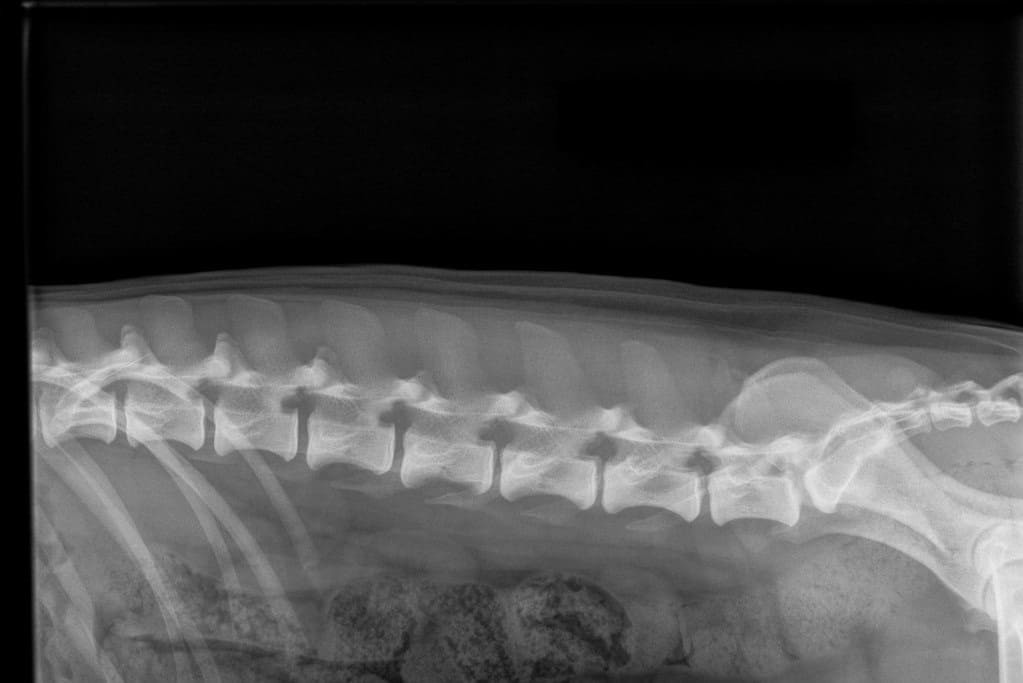

Kuvaamalla kaula-, rinta- ja lannerangan sekä ristiluun voi saada selkälausunnon LTV:stä, spondyloosista ja epämutoisista nikamista (VA). LTV- ja VA-lausunnon saa 12 kk ikäiselle koiralle ja spondyloosilausunnon 24 kk ikäiselle. Kennelliiton ohje selkärangan kuvaamiseen: https://www.kennelliitto.fi/lomakkeet/selkarangan-kuvauksen-suoritus

Suomen Kennelliiton LTV-luokittelu

LTV4; 8 lannenikamaa. L8 on puhdas lannenikama ja siinä on normaalit okahaarakkeet.